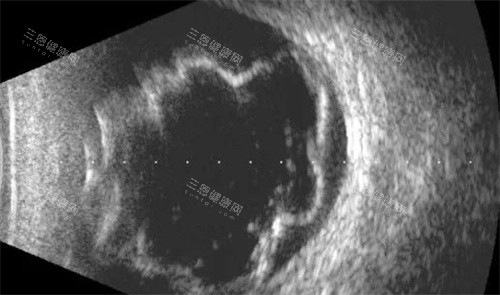

走进哈尔滨爱尔眼科医院的手术室,博士伦27G玻切超乳一体机正静静运转。这台能更准一些到微米级的设备,让医生能在不损伤健康组织的前提下,完成视网膜复位。2023年,该院眼底科团队凭借这项技术,成功为一位视网膜脱离伴严峻增殖膜的患者实施手术,术后视力从0.02改善到0.6。

急救体系的完善不仅体现在速度上。哈尔滨爱尔眼科医院建立的“术前-术中-术后”全流程管理系统,通过智能腕带实时监测患者生命体征,手术室配备的4K显微镜能将眼底图像放大200倍,确保每个操作细节都在掌控之中。